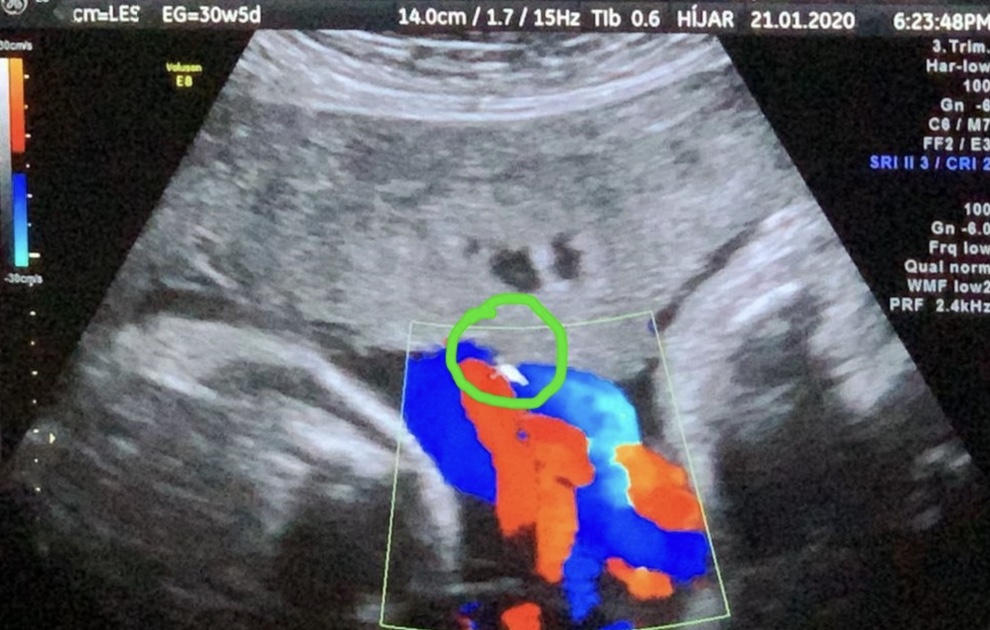

Paciente en decúbito dorsal. Barrido ecográfico previo para asegurar la localización placentaria. Ubicación de la zona de inserción del cordón umbilical.

Luego de ello se procedió a la TRANSFUSIÓN INTRAUTERINA: inyección de sangre de donante grupo O Rh negativo, se calculó 46cc según el aplicativo del Perinatology.